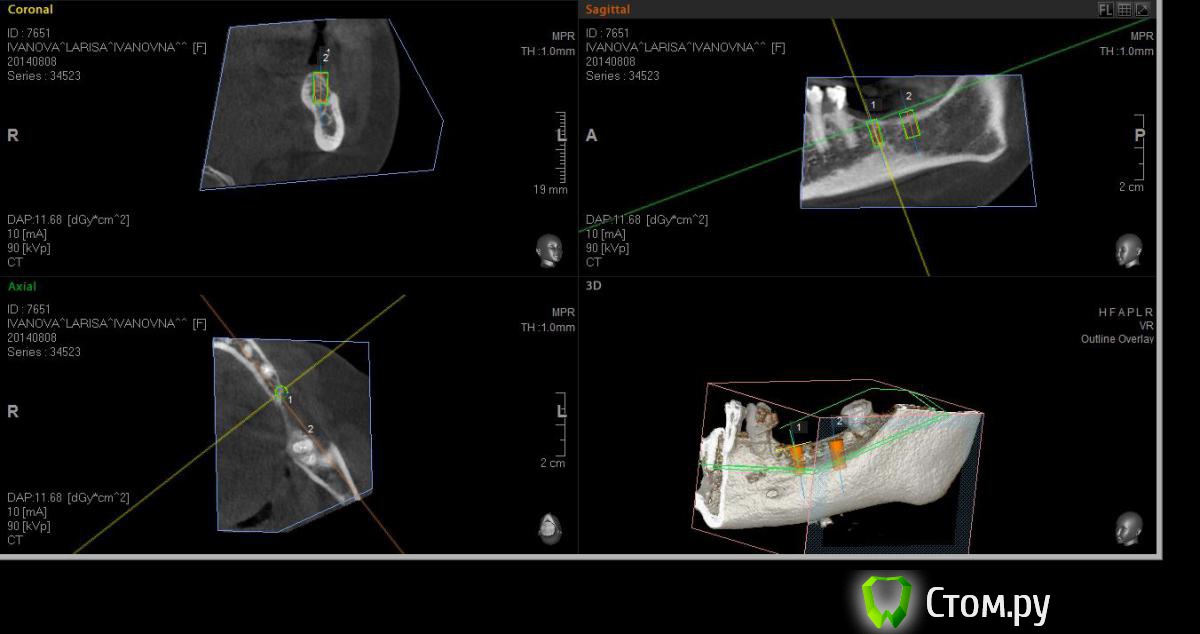

Neilrus Опубликовано 19 августа, 2014 Поделиться Опубликовано 19 августа, 2014 (изменено) Здравствуйте, форумчане-коллеги ) подскажите в очередной раз, пожалуйста.Возник вопрос, для опытных, безусловно, простой, помогите добрым советом.планируем имплантаты в область 36, 37. Длина никак больше 8 не входит, до нерва 10 с копейками и боюсь слишком тонкую кортикалку подязычно оставить.Расщепление из-за формы гребня не думаю, что получится, что-нибудь отломаю точно, хочу поставить как на фотографиях с нкр, голые витки вестибулярно перекрыть еволюшином толстым, припинить весибулярно и язычно если подлезу, либо подошью там.Как вы считаете, рабочая стратегия? Основной вопрос, могу я тут 100% ауто использовать? Объем же не большой, тут со сверления наберу, либо скребочком в зоне операции, заодно и принимающее ложе освежую это же сосидж? ничего не перепутал? И по поводу диаметров, 36 будет 3,75х8, а 37 4,2х8, не кротковаты? Просто у нас только МИС seven пока, либо 8, либо 10 длина. В 37 можно и 5 диаметр поставить, но опять же тонкая язычно остается. По той же причине отказался от длины 10 в 36зубе. Изменено 19 августа, 2014 пользователем Neilrus Ссылка на комментарий

Neilrus Опубликовано 26 августа, 2014 Автор Поделиться Опубликовано 26 августа, 2014 (изменено) +2 )) Во-первых, фиксация у Севена лучше, конечной фрезой на 50 оборотах понемногу наберете ауто. Если есть АСМ или Джилли - еще получите в области ретромолярки. Во-вторых, кости (на самом деле) "немного" больше, чем показывает конусник (это тоже плюс). Поэтому можно и 8, и 10 со стопером или под контролем. Ставьте на 0,5-1 ниже язычной. Выше ставить и обсыпать не рекомендую - разве что только под жесткую мембрану, иначе все уйдет. Язычно я бы не смещался, ставил как запланировано, по шаблону. И в обл. 37 до нерва более 11, так что все будет ОК. Потом придется поработать с мягкими тканями. Удачи!Спасибо. Поставил в итоге два севена десятки, у м4 резьба у шейки никакая по мне так, а шейка тут важна. Наклонил все равно слегка язычно, никуда не провалился, парестезии нет, немного у медиального было ей больно при дотягивании на 25 нютонах, сделал полоборота назад, ауто, потом микс с мр3, эволюшн три пина язычно, два вестибулярно. Швы в пн снимаю, пока полет нормальный, отек уже почти сошел. И по поводу взятия ауто, насколько я правильно понял всех лекторов моих, забор во время бурения только промежуточными сверлами, пилотное и финишное сверление всегда с водой. Нет? Изменено 26 августа, 2014 пользователем Neilrus Ссылка на комментарий